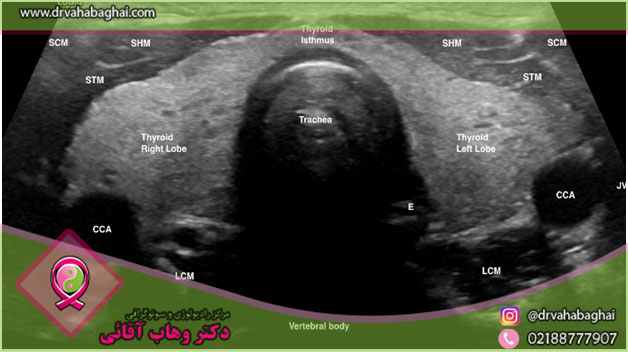

اگر به تازگی سونوگرافی تیروئید و گردن انجام داده باشید، آشنایی با نحوه تفسیر

نتایج سونوگرافی تیروئید و خواندن جواب آن قبل از مراجعه به متخصص میتواند برای

شما مفید باشد. سونوگرافی تیروئید یکی از روشهایی است که با کمک امواج صوتی میتوان

تصاویری از غده تیروئید را مشاهده کرد. با این روش ندولهای (تودهها) داخل غده تیروئید و در ناحیه گردن به راحتی

دیده میشود. اولتراسونیک یا سونوگرافی از تیروئید و گردن یک روش غیرتهاجمی، بدون

درد و عارضه است. در این مقاله به بررسی اصطلاحات رایج در تفسیر سونوگرافی گردن و

تیروئید میپردازیم.

این روش تصویربرداری میتواند اندازه، شکل

و موقعیت طبیعی غده تیروئید را به خوبی نشان دهد.